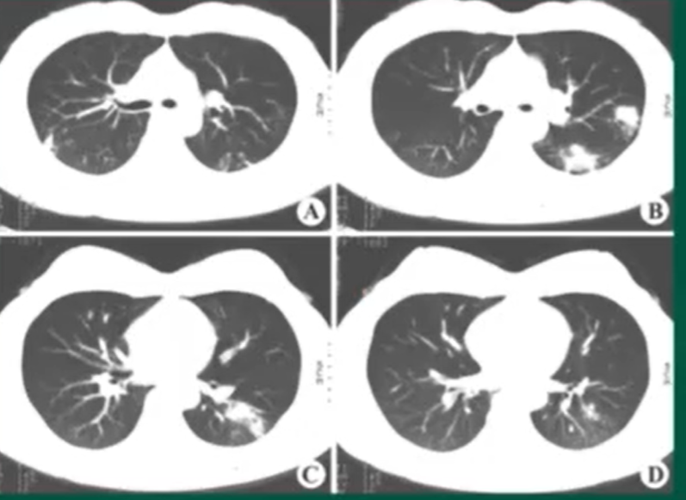

图6c 女性,35岁,职业暴露,大片实变影,内见充气支气管征